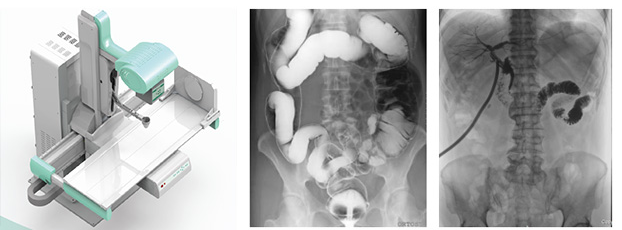

3、要拥有适宜床体高度的动态检查床及全面的床体运动功能,以轻松实现各种普通及特殊造影检查,如食道造影、消化道造影、结肠双对比造影、T管造影、静脉肾盂造影(IVP)等。同时动态dr要支持医生回放造影视频,并可以抽帧,辅助疾病诊断。